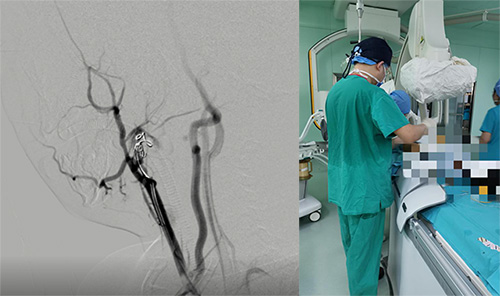

患儿迅速完善各项术前相关检查,麻醉科积极协调相关人员和手术间,急诊行颈动脉栓塞术,封堵颈动脉破裂口。整个手术过程惊心动魄,稍有偏差,患儿极有可能发生瘤体破裂大出血,心脏外科二科李志强主任、成伟副主任医师顶住压力,最终成功完成手术。

此次微创腔内手术后仅有1mm的皮肤穿刺点,避免了开放手术的创伤。患儿术后转入心脏外科二科继续治疗。术后第二天,患儿颈部包块明显缩小,顺利自主进食。